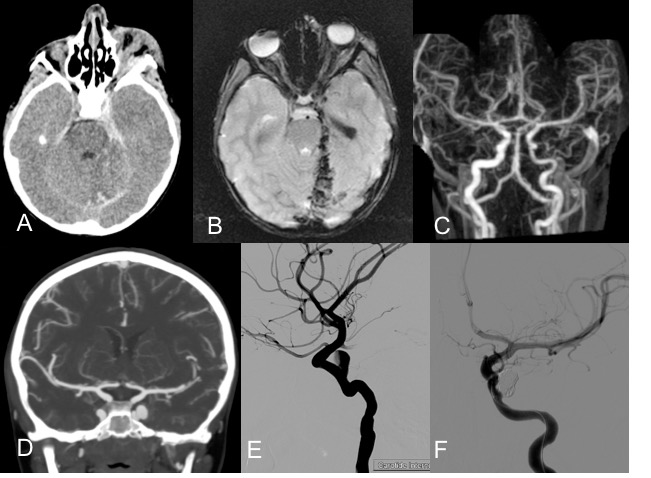

plaie pénétrante de la paupière inférieure gauche. A, B : l’imagerie montre des lésions intracrâniennes liées à une pénétration par la fente sphénoïdale, dans le sinus caverneux et la cavité crânienne. C : plaie et spasme de la carotide gauche. D, E : développement progressif d’un anévrisme traumatique de la carotide, F : traitement de l’anévrysme par embolisation - lésion de l’étage postérieur de la base du crâne